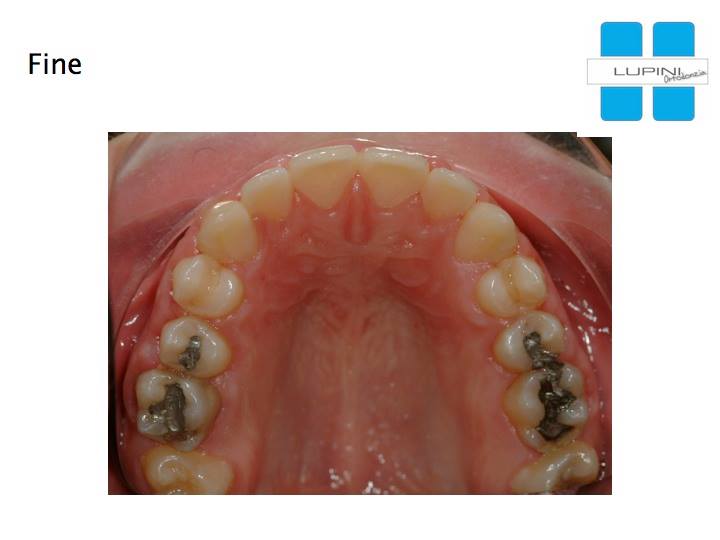

Palato Stretto Adolescente - Trattamento Ortodontico-ortopedico in Dentatura Permanente